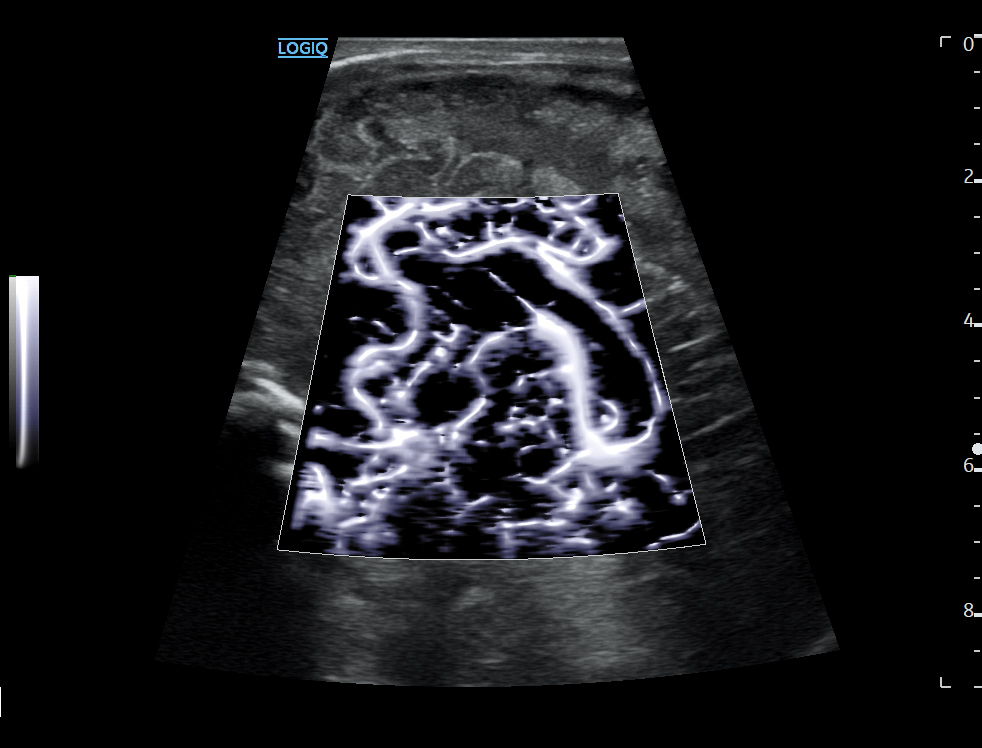

-对比增强超声- ce setează pentru b超检查cu substanță对比noi标准